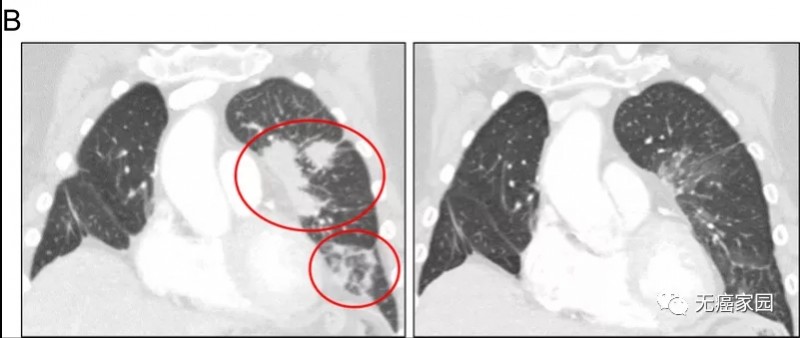

再次使用单独的个体患者研究新药 (IND)方案,每天服用奥希替尼80 mg+BLU-667 200 mg,持续2周,然后每天服用300 mg的BLU 667,持续2周后最终升级至每天400 mg。8周后的扫描也显示了显著的临床改善,影像学成像肿瘤缩小了78%!

患者2对奥希替尼和 BLU-667 的治疗反应,与基线(左)相比,左上叶和左下叶肺混浊(右;圈出)有显著改善。